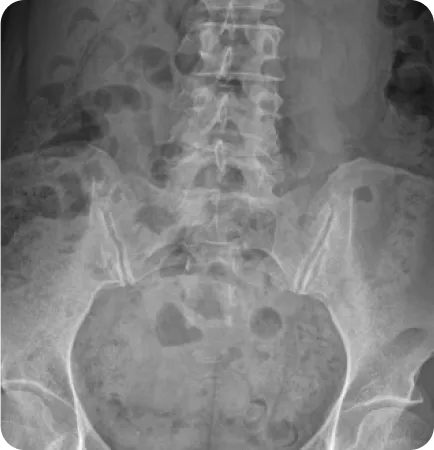

성인의 80%~90%에서 골반 부정렬이 발견되었으며,

그 중 3분의 1은 무증상, 3분의 2는 요통, 골반통 등의 증상을 호소한다.

Wolf Schamberger - The Malalignment Syndrome 中